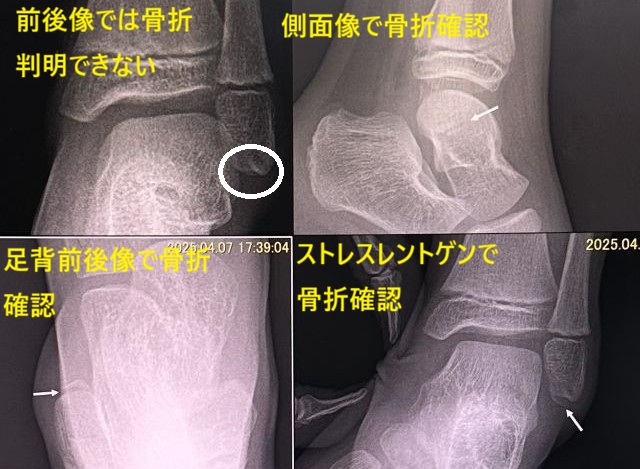

診断の際に多方向撮影やストレスレントゲン撮影で確認されることが多々あります。時に外反(外返し)が強制されて起こる内果剥離骨折も経験します。

診断はレントゲン検査と超音波検査です。レントゲンではケガをした時の足首の状態を再現したストレスレントゲン撮影が診断に有益です(断裂例)。また、超音波検査は動的に損傷部を観察できるため有益な情報を与えてくれます。